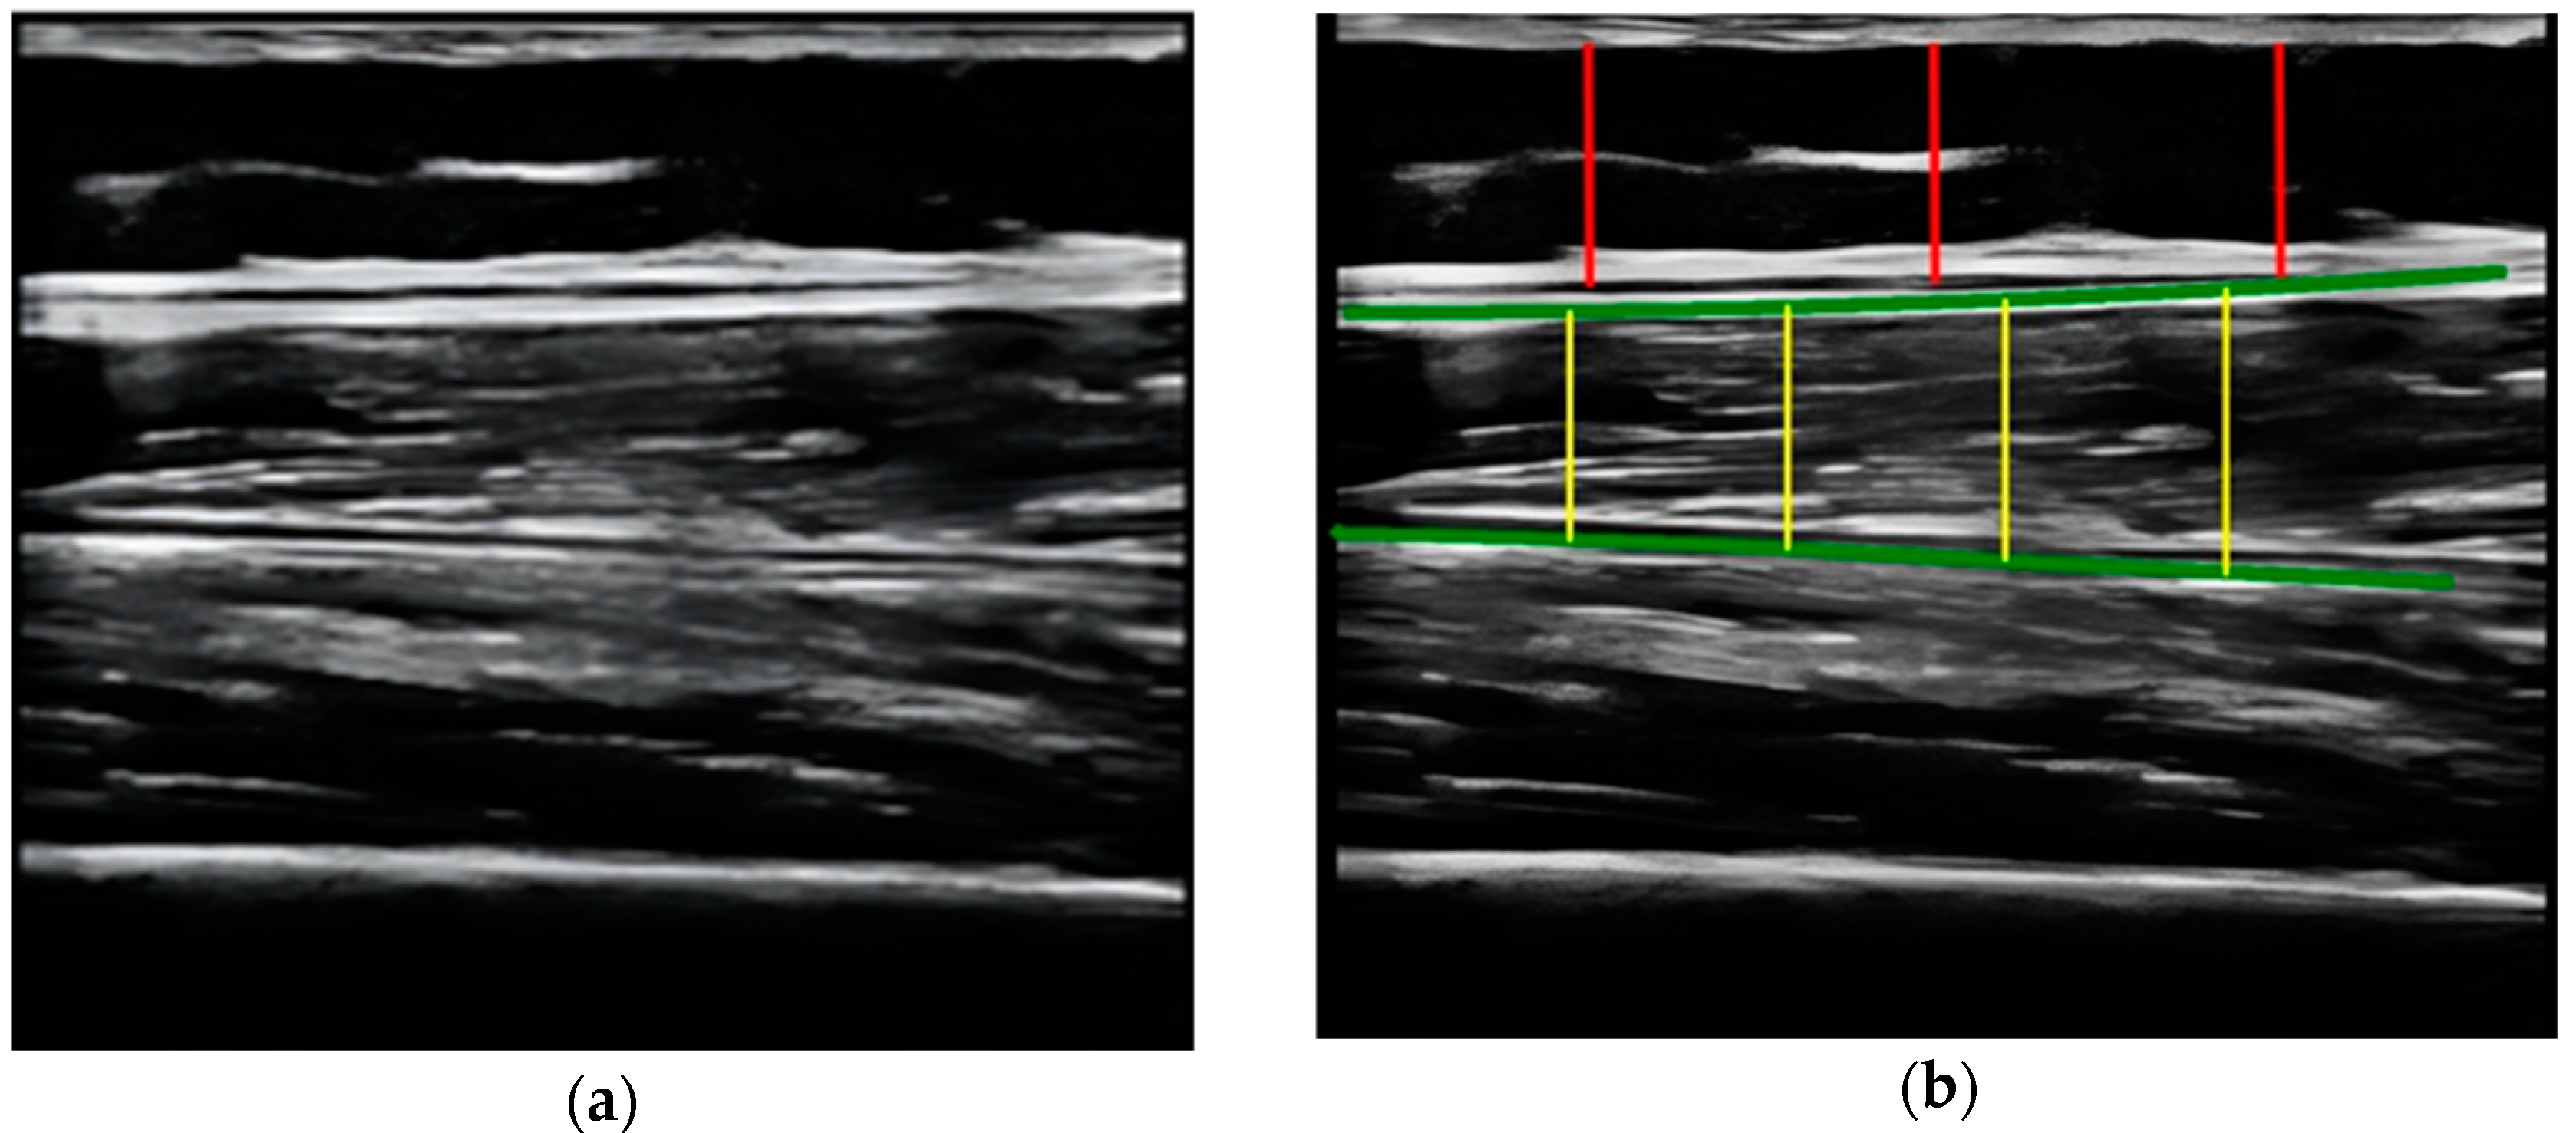

Figure 4. (a) Acquired raw ultrasound image of the unilateral (right) quadriceps rectus femoris muscle in the longitudinal plane obtained by rater 1 and scaled by PIIXMEDTM (rater 2—method B); (b) PIIXMEDTM processing (i.e., rater 2—method B) of the automatically segmented longitudinal ultrasound image, upper and deep aponeurosis (green color), to obtain the results of the SFT (three red lines and their mean value) parameter and the longitudinal thickness (four yellow lines and their mean value), MT, not used in this study. - Calculate and evaluate the inter-rater reliability of quantitative muscle architecture parameters (MAP) of the unilateral (right) RF measurements performed by the expert evaluator (rater 1) (i.e., method A) against the measurements using the automated PIIXMEDTM Ultrasound Imaging System (rater 2) (Dawako Medtech S.L., Valencia, Spain) (i.e., method B) on the same acquired raw images.

The MAP variables measured and analyzed by PIIXMEDTM in this study were the RF thickness and cross-sectional area in the transverse plane (MT, and CSA) and the subcutaneous fat thickness (SFT) in its longitudinal plane.